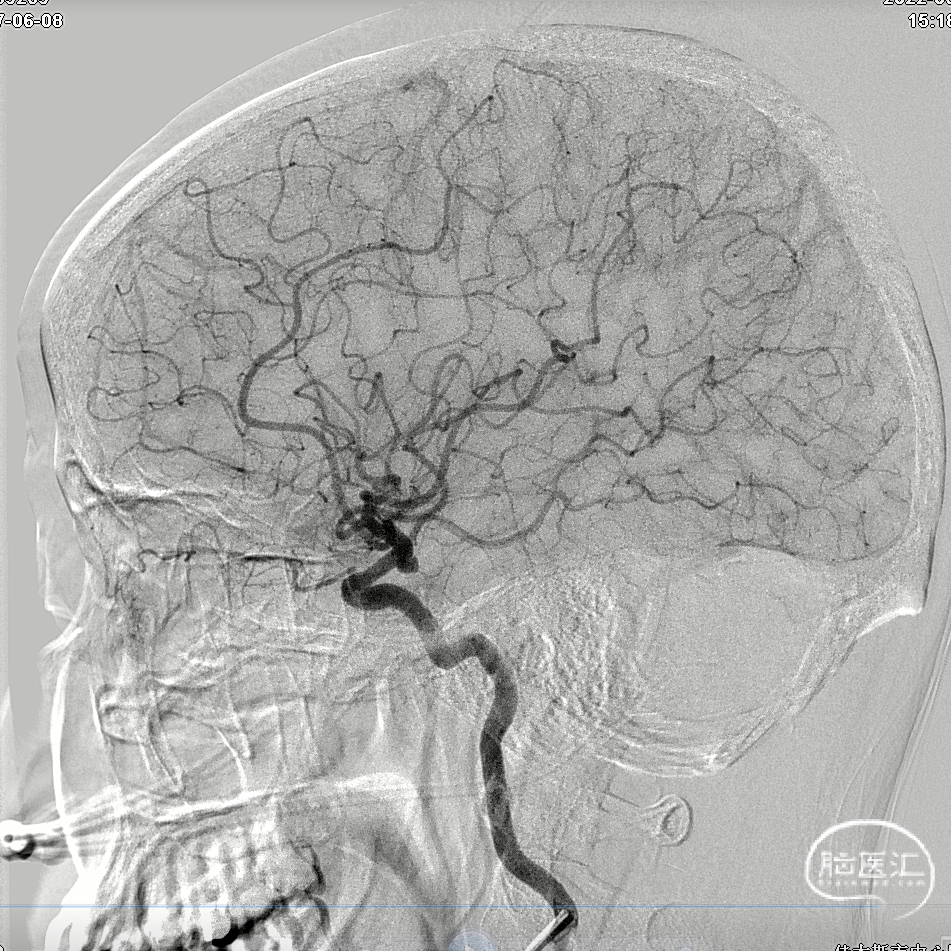

DSA正侧位

左侧颈内动脉后交通段动脉瘤

动脉瘤尺寸3.5mm*2mm

瘤颈口约2mm

左侧颈内动脉后交通段动脉瘤,动脉瘤较小,填塞过程容易破裂出血,后交通动脉较粗大,需要保留后交通动脉,预留支架导管,必要时可释放支架保护颈内动脉及后交通动脉。

首个弹簧圈成篮后造影

填塞第二枚弹簧圈后造影

动脉瘤填塞后造影(即刻)